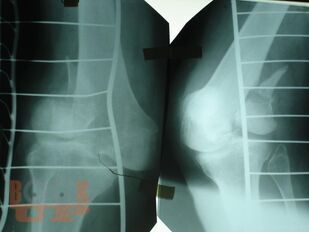

Учебное пособие содержит необходимую информацию для врачей по вопросам оказания специализированной помощи пострадавшим с тяжелой травмой костей нижних конечностей. Подробно освещены вопросы патогенеза шока как основной причины развития травматической болезни, а также тактики оказания специализированной и высоко квалифицированной помощи пострадавшим с тяжелыми монолокальными и множественными переломами костей нижних конечностей в зависимости от периода развития травматической болезни. Особое внимание уделено профилактике и лечению ранних осложнений тяжелых переломов костей нижних конечностей – синдрому жировой эмболии, тромбоэмболическим осложнениям. В пособии обобщен более чем 30- летний опыт лечения пациентов с тяжелой травмой костей нижних конечностей.